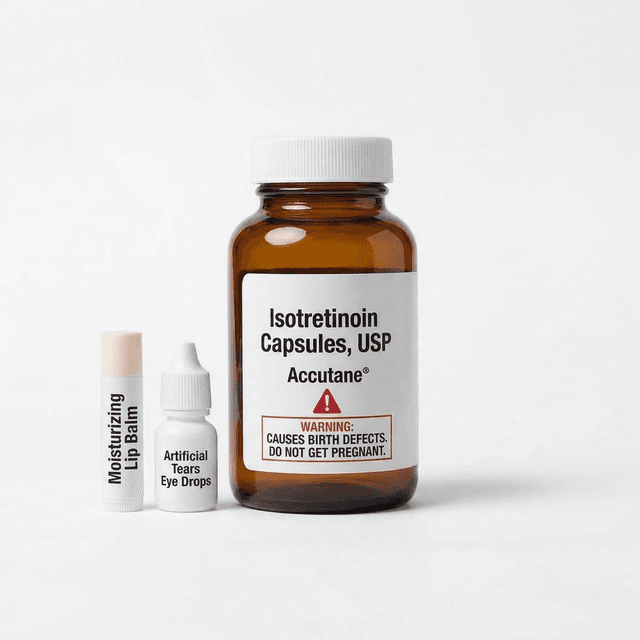

Accutane for Teens: Everything Parents and Teens Need to Know

Accutane (isotretinoin) clears severe acne in about 85% of patients, but the process involves monthly blood tests, strict pregnancy prevention, and several months of very dry everything. Here's what the experience actually looks like.

Isotretinoin (Accutane) for Acne: Comprehensive Side Effect Profile

Isotretinoin offers the highest acne clearance rates (80-90%) but requires accepting universal severe dryness, monthly blood monitoring, strict birth control requirements, and potential serious side effects including mood changes and organ toxicity.